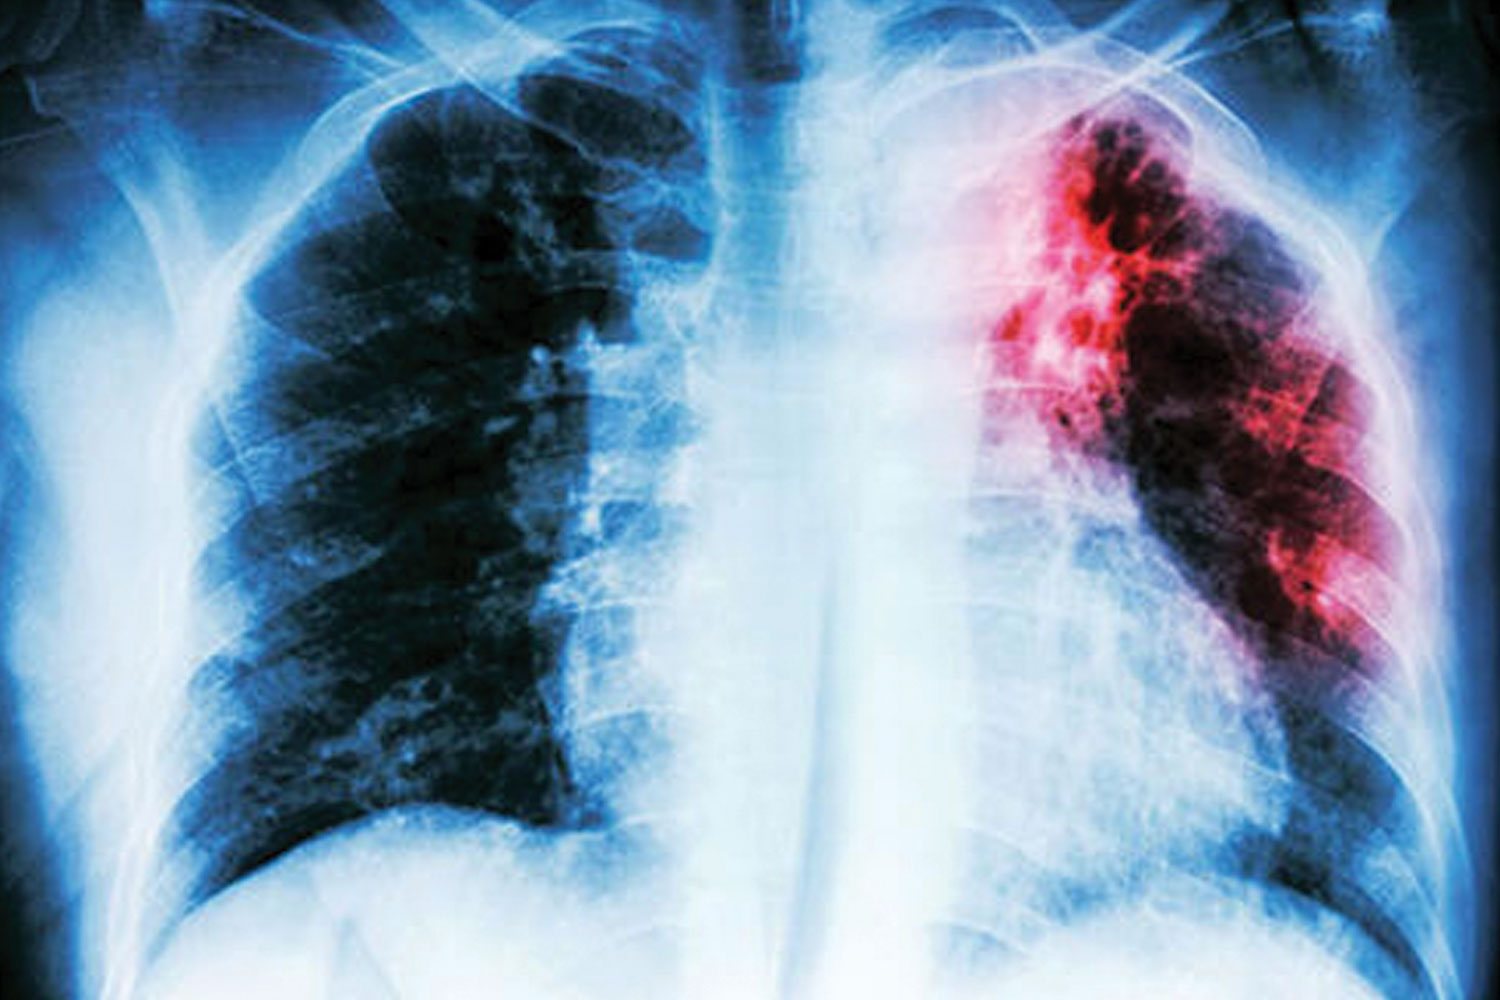

Özellikle 65 yaşı geçenler için zaten önemli bir korunma yöntemi olan zatürre aşısı, COVID-19 pandemisi nedeniyle sağlık gündemimizin ana maddelerinden biri haline geldi.

Nedeni malum, pandemide pek çok insanımızı akut akciğer iltihaplanması yani zatürre nedeniyle kaybettik. Zira yeni koronavirüsün en önemli özelliklerinden biri, onu diğer koronavirüslerden ayıran başlıca karakteri hızla akciğerlere yerleşme ve adeta boğulmaları andıran nefes darlıklarıyla karakterli ağır bir zatürreye yol açması. İşte bu nedenle özellikle önümüzdeki günlerde muhtemel bir zatürreden korunmak ve bu nedenle de aşılanmak mühim bir ayrıntı.